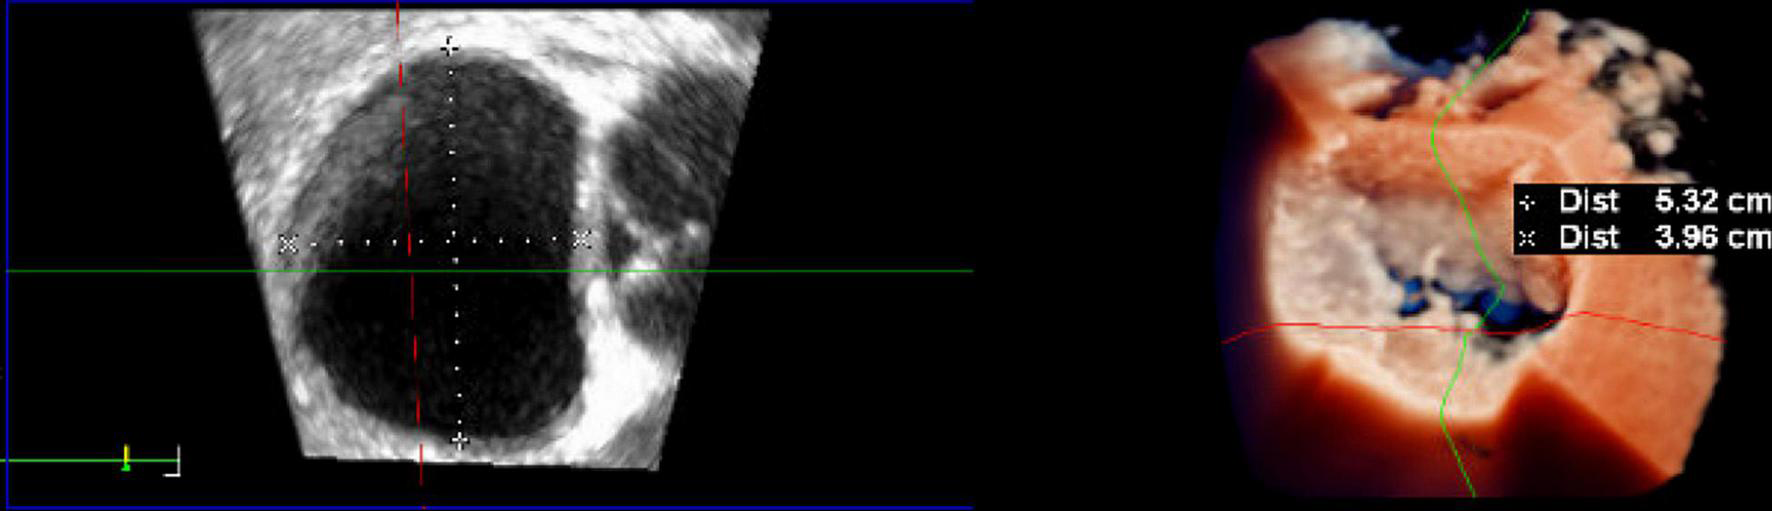

After each deployment of the device, knot position should be checked with 3D (“surgical”) TEE view (Figure 6), visualizing the mitral valve as seen from the left atrium. The upper leaflet in this view is the anterior leaflet, the lower leaflet in this view is the posterior leaflet. The scallops are seen from left-to-right as follows: A1/P1-A2/P2-A3/P3.

FIGURE 6

Intraoperative three-dimensional TrueVue photo-realistic rendering of the mitral valve before repair with the HARPOON System. A surgical view of the atrial side of the mitral valve is shown on the right. The anteroposterior diameter of the mitral valve is 3.96 cm.